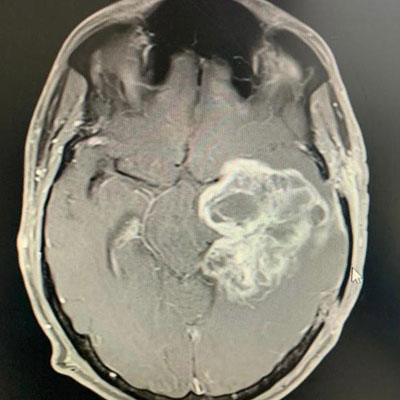

Surgical Highlights